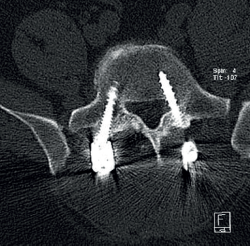

Cincuenta días tras el accidente se realizó fusión lumbar instrumentada L4-L5 con inserción de dispositivo intersomático por vía transforaminal derecha. En el segundo día postoperatorio presentó empeoramiento del dolor, objetivándose en la tomografía computarizada (Figura 2) malposición del tornillo L5 izquierdo que invadía el canal. Se reintervino a los 5 días corrigiendo el trayecto del tornillo. Sin embargo, persistió el dolor. La revaluación del caso, sumada a los hallazgos de EMG, motivó estudios complementarios de pierna y trayecto ciático (Figuras 3 y 4), detectándose una masa tumoral en el fémur izquierdo compatible con sarcoma fusocelular.

Figura 2. Tomografía computarizada lumbar postoperatoria en corte axial. Tornillo pedicular izquierdo de L5 mal posicionado, con violación de la pared medial del pedículo e invasión parcial del canal vertebral.